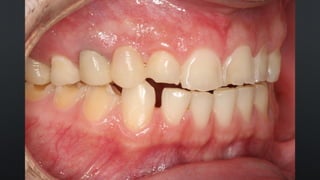

• OCLUSÃO FISIOLÓGICA, DETERMINADA PELA POSIÇÃO DO CÔNDILO

RELAÇÃO ENTRE ARCOS

RELAÇÃO CÊNTRICA (RC)

• O CÔNDILO E O DISCO SE ENCONTRAM EM UMA POSIÇÃO MAIS SUPERIOR E

ANTERIOR NA FOSSA ARTICULAR

• POSIÇÃO DE REABILITAÇÃO EM PACIENTES DESDENTADOS OU COM OCLUSÃO

INSTÁVEL

• TODO PACIENTE PODE SER LEVADA À RC

• OCLUSÃO FISIOLÓGICA,DETERMINADA PELA POSIÇÃO DO CÔNDILO RELAÇÃO ENTRE ARCOS RELAÇÃO CÊNTRICA (RC) • O CÔNDILO E O DISCO SE ENCONTRAM EM UMA POSIÇÃO MAIS SUPERIOR E ANTERIOR NA FOSSA ARTICULAR • POSIÇÃO DE REABILITAÇÃO EM PACIENTES DESDENTADOS OU COM OCLUSÃO INSTÁVEL

• 61.

• TODO PACIENTEPODE SER LEVADA À RC RELAÇÃO ENTRE ARCOS RELAÇÃO CÊNTRICA (RC) - MANIPULAÇÃO BILATERAL - LÂMINAS DE LONG